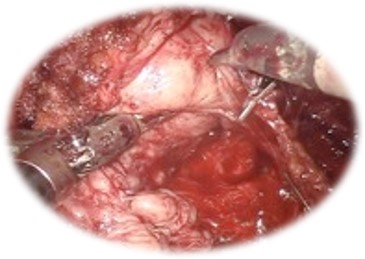

Nefrectomia radicală robotică:

• Presupune îndepărtarea rinichiului afectat tumoral împreună cu fascia Gerota în bloc și a ganglionilor limfatici regionali

• Este indicată în cazul tumorilor voluminoase renale

• Sângerare redusă

• Risc scăzut de complicații intra/ postoperatorii